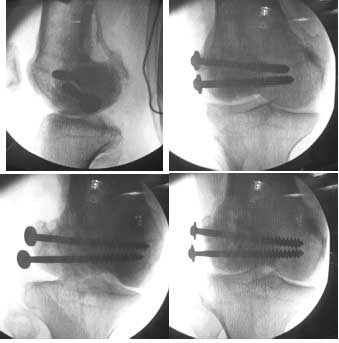

This was fixed temporarily, bone grafted with tricortical struts, and fixed by two cancellous screws. The fragment was not large enough to afford any fixation to a plate or such implant, and the screws held it compressed well to the rest of the distal femur.

Post-op - limb is well aligned, rom 0-30, but I am not pushing that right now, for the next two or three weeks.

Further plan - hope that the screws hold the fragment appropriately till union, but if the stability on table is anything to judge by, that should not be a problem.

Pictures attached.

A good job, though personally I would have preferred the screws a bit longer.